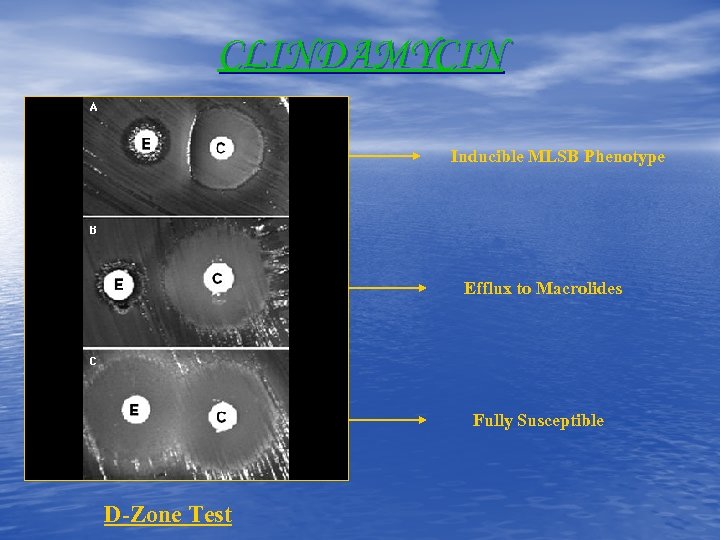

CLINDAMYCIN Inducible MLSB Phenotype Efflux to Macrolides Fully Susceptible D-Zone Test

CLINDAMYCIN Inducible MLSB Phenotype Efflux to Macrolides Fully Susceptible D-Zone Test